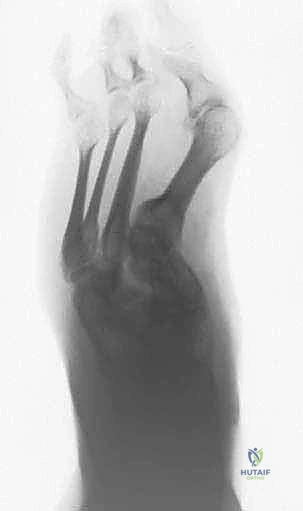

تنظير عظم منتصف القدم بالتثبيت الخارجي هو إجراء جراحي طفيف التوغل يستخدم لتصحيح تشوهات منتصف القدم المعقدة، مستخدمًا تقنيات حديثة مثل منشار الجيجلي والتثبيت الخارجي لإعادة محاذاة القدم، تخفيف الألم، واستعادة الوظيفة الطبيعية للمشي بدقة عالية.

الخلاصة الطبية السريعة: يُعد إجراء "تنظير عظم منتصف القدم بالتثبيت الخارجي" (Percutaneous Midfoot Osteotomy with External Fixation) ثورة في عالم جراحة العظام، وهو إجراء جراحي طفيف التوغل يُستخدم لتصحيح تشوهات منتصف القدم المعقدة بأعلى درجات الدقة. يعتمد هذا الإجراء على تقنيات حديثة تتضمن استخدام منشار الجيجلي (Gigli Saw) لعمل قطوع عظمية دقيقة عبر شقوق صغيرة جداً، متبوعاً بتطبيق جهاز التثبيت الخارجي لإعادة محاذاة القدم تدريجياً. يهدف هذا التدخل المتقدم إلى تخفيف الألم المزمن، وتصحيح التشوه الهيكلي، واستعادة الوظيفة الطبيعية للمشي، مع الحفاظ التام على الأنسجة الرخوة والأوعية الدموية، وذلك تحت إشراف الأستاذ الدكتور محمد هطيف، رائد جراحة العظام في اليمن.

عندما تزور عيادة الأستاذ الدكتور محمد هطيف في صنعاء، يتم إجراء تقييم شامل لحالتك يشمل الفحص السريري الدقيق، وصور الأشعة السينية (X-rays) أثناء الوقوف، والتصوير المقطعي المحوسب (CT Scan) ثلاثي الأبعاد لفهم الهندسة المكانية للتشوه بدقة. بناءً على ذلك، يتم تحديد مسار العلاج.

من هنا، تبرز عبقرية تقنية "تنظير عظم منتصف القدم بالتثبيت الخارجي". دعونا نقارن بين الطريقتين لندرك حجم التطور:

| وجه المقارنة | الجراحة المفتوحة التقليدية (Traditional Open Osteotomy) | تنظير العظم طفيف التوغل بالتثبيت الخارجي (Percutaneous with External Fixation) |

|---|---|---|

| حجم الشق الجراحي | شقوق كبيرة جداً (10-15 سم) لكشف العظام بالكامل. | شقوق دقيقة جداً (ثقوب صغيرة لا تتجاوز 1 سم) لإدخال الأدوات. |

| التروية الدموية للعظم | يتم تجريد العظم من السمحاق (الغلاف المغذي)، مما يضعف التروية الدموية ويبطئ الالتئام. | حفاظ تام على السمحاق والتروية الدموية، مما يسرع التئام العظام بشكل مذهل. |

| مخاطر العدوى (Infection) | عالية نسبياً، خاصة لدى مرضى السكري وضعاف المناعة بسبب كبر حجم الجرح. | منخفضة جداً، بفضل الشقوق الدقيقة وعدم تعرض الأنسجة العميقة للهواء. |

| طريقة التثبيت | شرائح ومسامير داخلية (Internal Fixation) تبقى في الجسم، وقد تتطلب جراحة أخرى لإزالتها إذا سببت إزعاجاً. | جهاز تثبيت خارجي (External Fixator) يتم إزالته في العيادة بعد التئام العظم دون جراحة إضافية. |

| إمكانية التعديل بعد الجراحة | غير ممكنة؛ الزاوية التي تُثبت في غرفة العمليات هي النهائية. | ميزة استثنائية: يمكن للطبيب تعديل زوايا التثبيت الخارجي تدريجياً في العيادة للوصول إلى المحاذاة المثالية بنسبة 100%. |

| التعافي وتخفيف الألم | فترة نقاهة طويلة، ألم شديد بعد الجراحة. | تعافي أسرع، ألم أقل بكثير، وإمكانية تحميل الوزن الجزئي في وقت مبكر. |